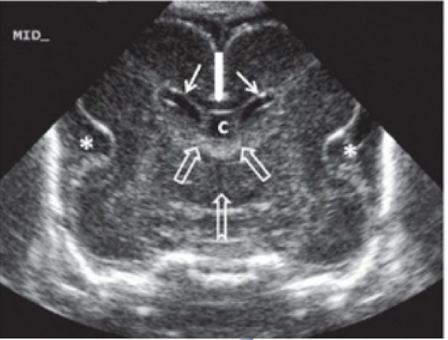

3rd ventricle

located centrally in the brain

inferior to the lateral ventricles

typically collapsed and only enlarged with pathology

cave septum pellucidum (CSP)

fluid filled, midline structure

located between the anterior flax and 3rd ventricle

two echogenic lines lateral to the falx

cerebellum

divided into two hemisphere that are connected by the vermis

hypoechoic and barbell butterfly shaped

measurement should correspond to GA after 16w

evaluate shape (banana shape associated with Arnold chair II malformation)